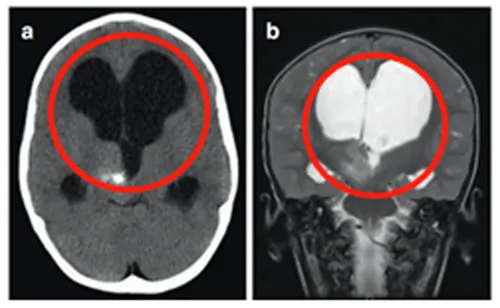

马修起初仅仅是因为呕吐,再加上头偏大,所以父母带着他去医院检查才发现右侧丘脑存在一个病变,且伴随钙化以及后三脑室的梗阻,继而引发了脑积水,这些共同导致了影像上看到的异常肿大。

症状不严重,手术风险太大,做完可能比现在更差,医生评估不具有手术指征。然而,肿瘤一直长大,而且长出了很多小的囊肿。同侧内囊(负责人体肢体运动)也向前外侧移位,导致马修从左上肢震颤到急性偏瘫。

马修先是接受了神经导航和超声引导下的活检,证实肿瘤为WHO I级毛细胞星形细胞瘤。

为了治疗多发囊肿,他们找到INC鲁特卡教授植入ommaya囊并在超声引导下将导管插入肿瘤囊性成分。MRI显示囊性占位解除,脑室慢慢恢复正常。